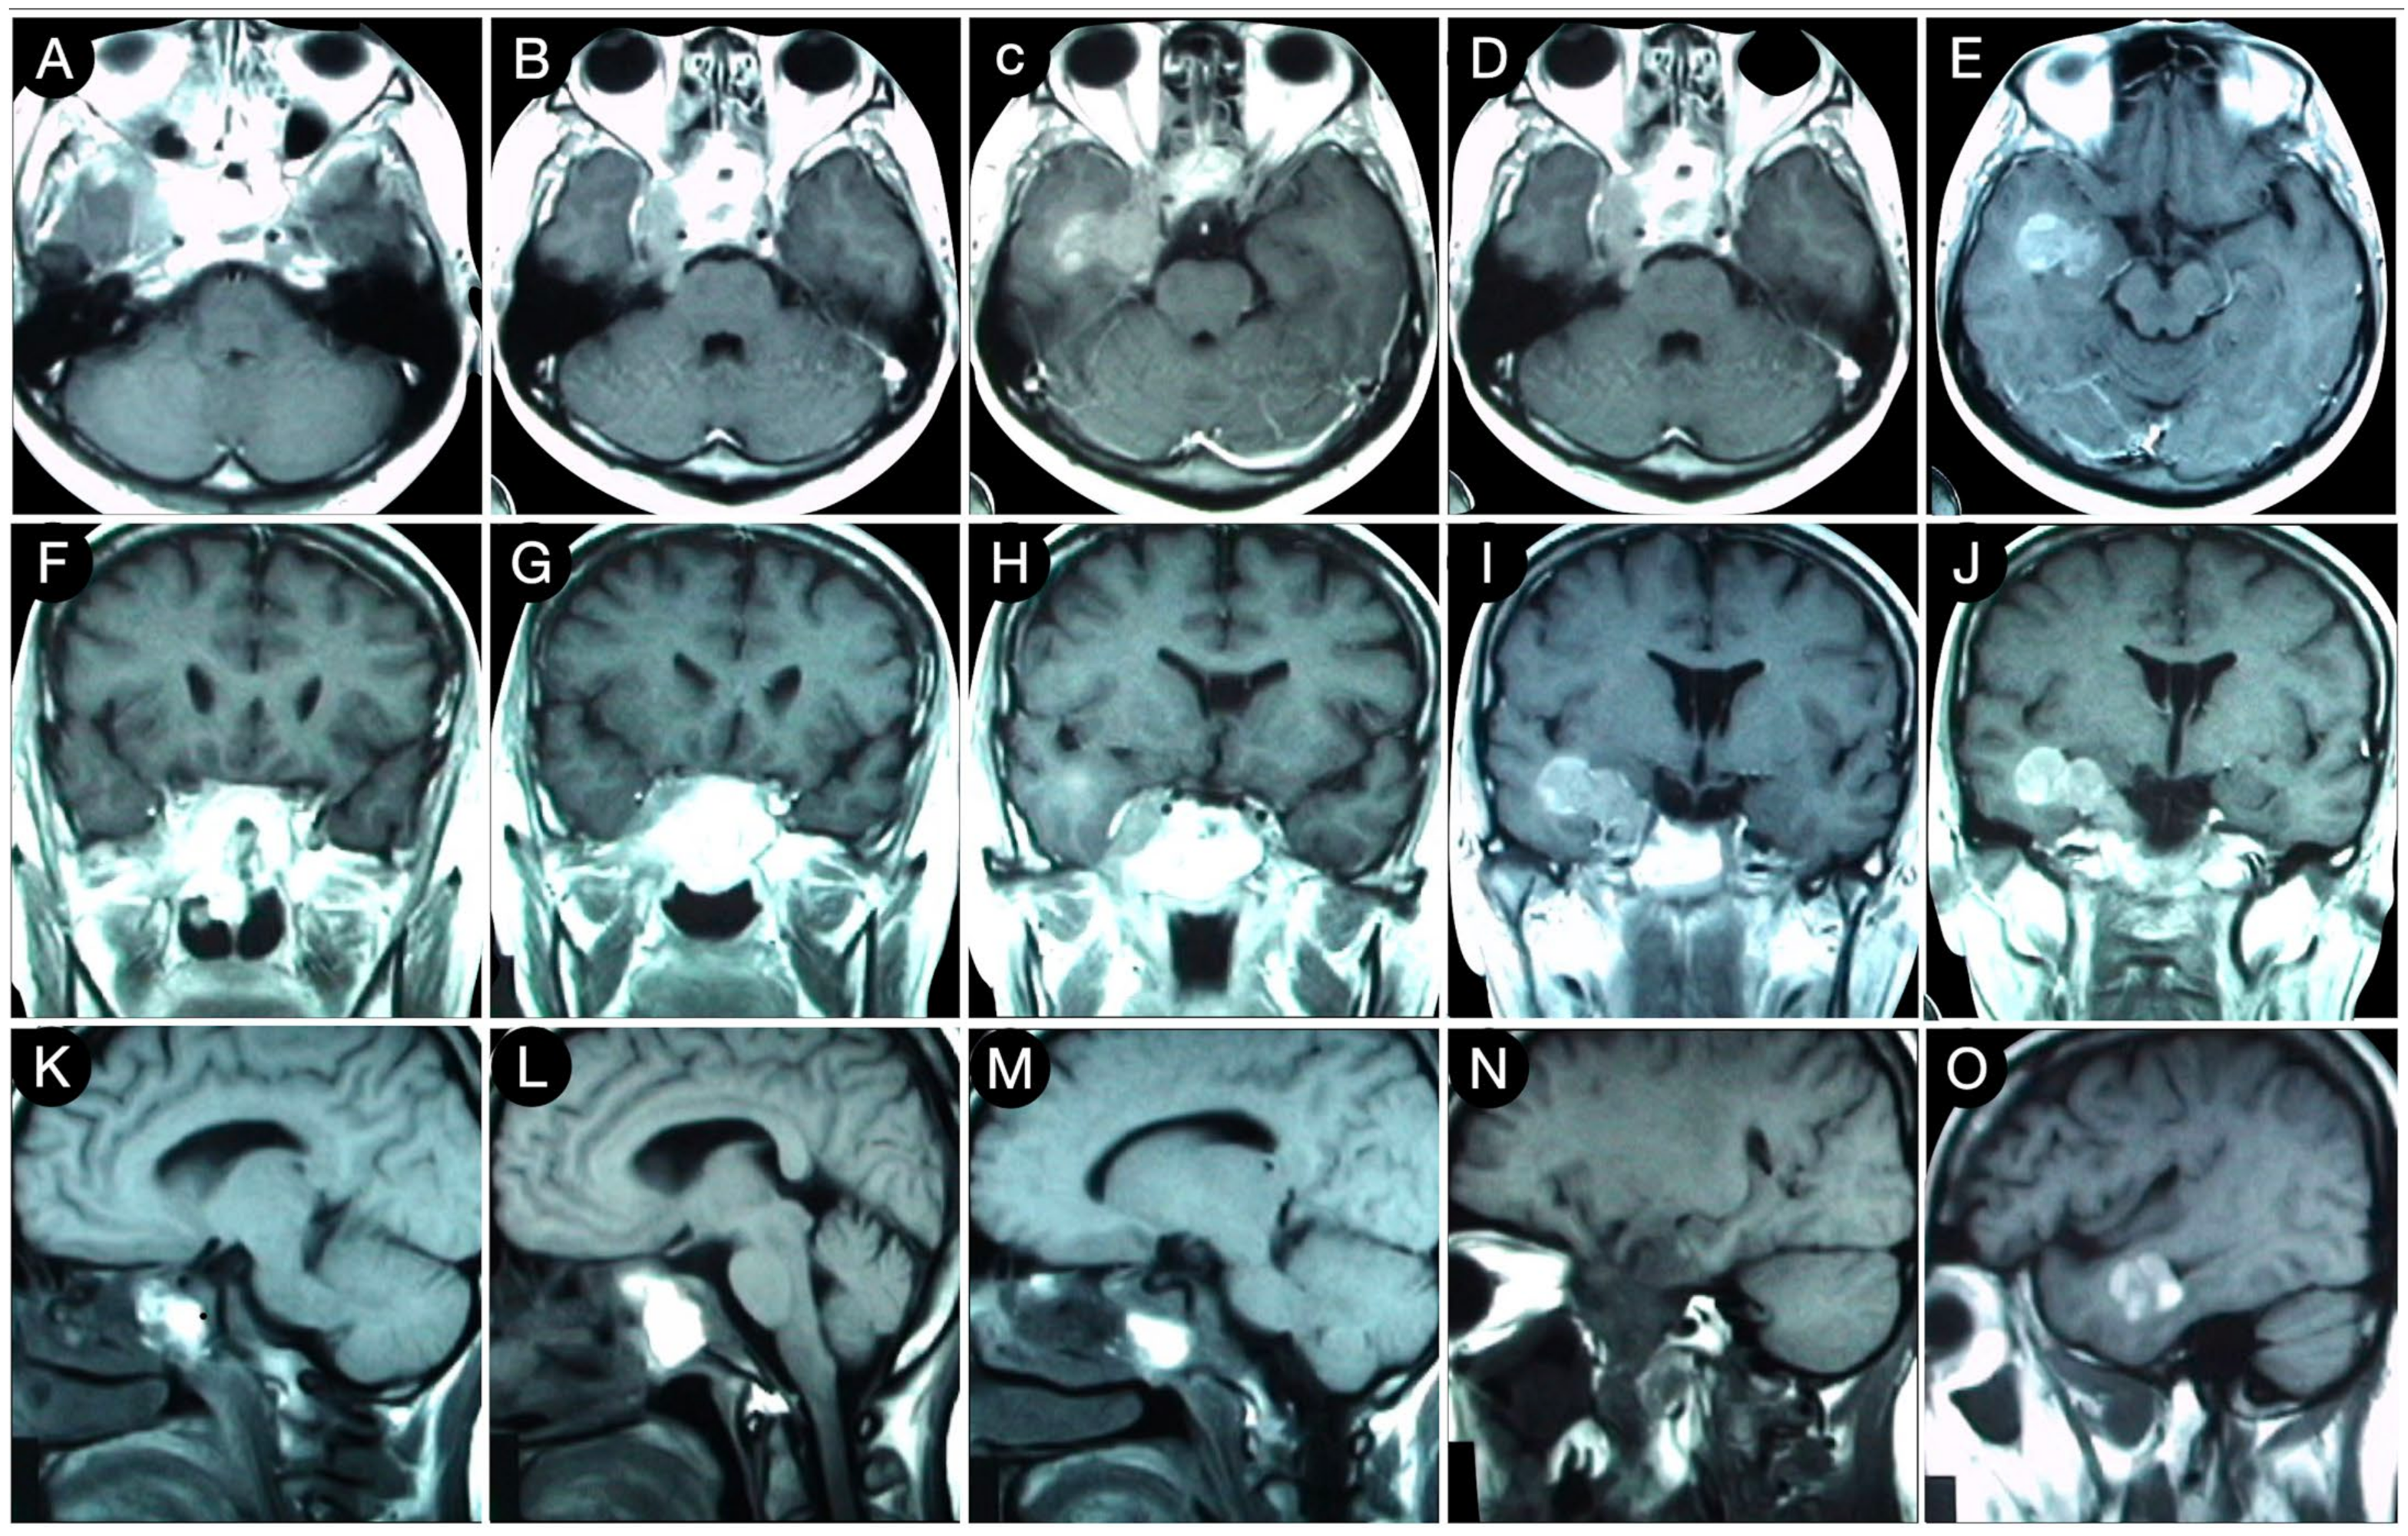

3.2.2. Case #3: Paramedian Pattern of Growth with Parenchymal Invasion

3.3.1. Case #4: Involvement of the Middle Skull Base with Parenchymal Invasion

3.3.2. Case #5: Extension beyond the Lateral Wall of the Cavernous Sinus

3.3.3. Case #6: Encasement of the Posterior Communicating and Anterior Choroidal Artery

Case #7: Encasement of the Paraclinoid and Supraclinoid Internal Carotid Artery

Case #8: Aggressive ACTH Tumor with Multiple Recurrences